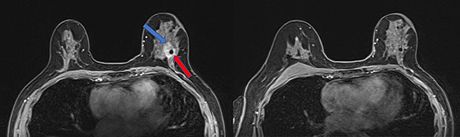

Ova dva snimka magnetnom rezonancom (MRI) napravljena su u razmaku od 10 meseci. Sa leve strane, plava strelica pokazuje na ivicu tumora dojke, a crvena strelica locira snimak biopsije, koji se pojavljuje kao crna tačka. MRI sa desne strane, koji uključuje snimak biopsije, pokazuje da je tumor nestao nakon jedne, ciljane doze zračenja i antihormonske terapije Foto: UT Southwestern Medical Center